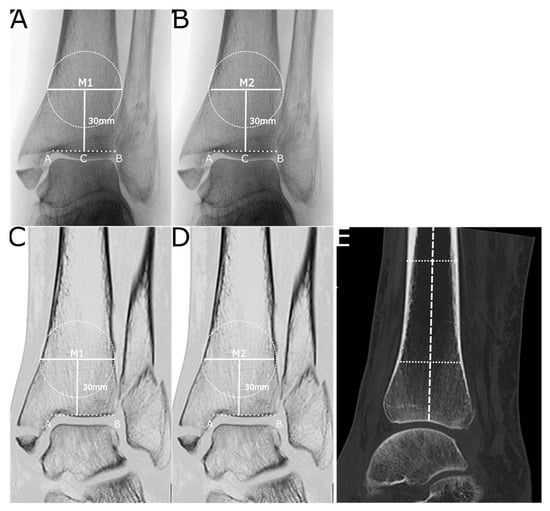

2.2. Radiographic Analysis

3.2. Radiographic Analysis